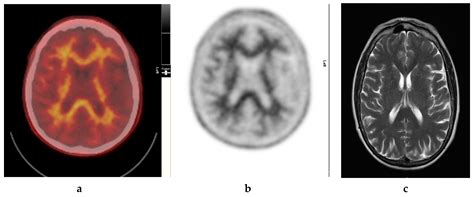

Combination Imaging

Combining Amyloid PET Imaging with other imaging modalities, such as magnetic resonance imaging (MRI) or functional PET, can provide a more comprehensive assessment of brain structure and function. This multi-modal approach could improve diagnostic accuracy and treatment planning.